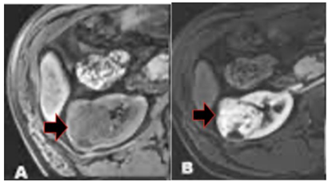

Observe a imagem a seguir.

As três áreas com asteriscos correspondem, respectivamente, às seguintes estruturas:

A seta na ressonância magnética acima está indicando a seguinte estrutura:

Com relação à lesão acima, assinalada pela seta, é correto afirmar que se trata de